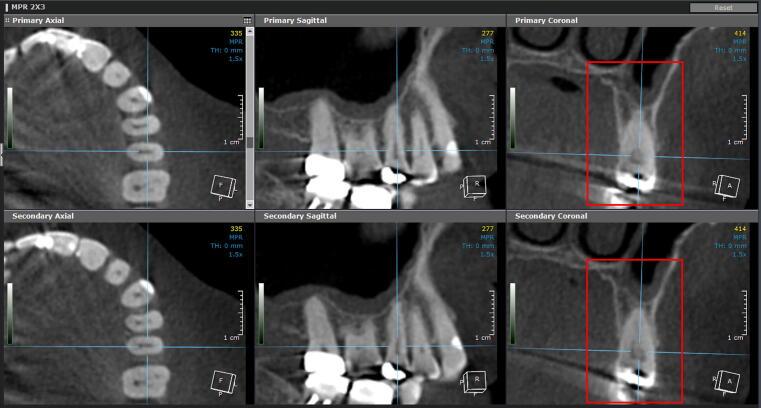

Răng di chuyển trong xương thông qua quá trình tiêu và tái tạo xương, nhưng quá trình này luôn có giới hạn phụ thuộc vào độ dày xương ổ răng, mật độ xương và vị trí chân răng ban đầu, và khi vượt qua giới hạn này, xương không thể tái tạo kịp dẫn đến các biến chứng như tiêu chân răng, tụt lợi hoặc răng di chuyển ra khỏi xương. Điều quan trọng cần hiểu là những biến chứng này không phải do niềng răng tự thân gây ra mà là hệ quả của một kế hoạch điều trị không tôn trọng giới hạn sinh học.

Trong X-Matrix, an toàn được đảm bảo bằng việc phân tích CBCT để xác định chính xác biên xương, đánh giá vị trí chân răng trước điều trị và mô phỏng toàn bộ đường đi của chân răng trong quá trình dịch chuyển, từ đó đảm bảo rằng mọi di chuyển đều nằm trong giới hạn có thể kiểm soát và không tạo ra tổn thương cho mô nâng đỡ.

Tiêu chuẩn sinh học (an toàn) yêu cầu chân răng nằm hoàn toàn trong giới hạn xương ổ, không có dấu hiệu tiêu chân răng hoặc tổn thương mô nâng đỡ. Đây là tiêu chí bắt buộc và được kiểm tra bằng phim X-quang, nhằm đảm bảo rằng kết quả đạt được không đánh đổi bằng tổn thương mô.